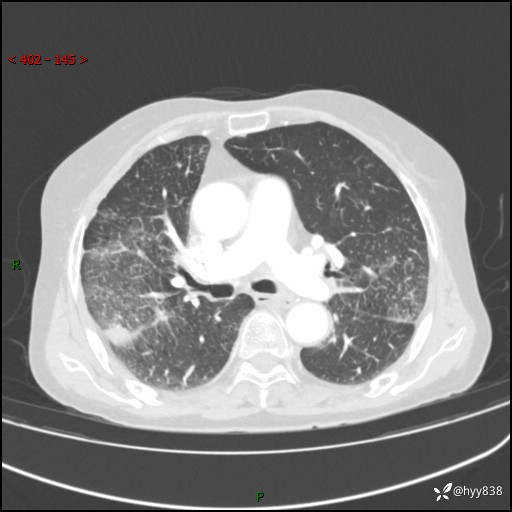

胸部CT增强(外院平扫)